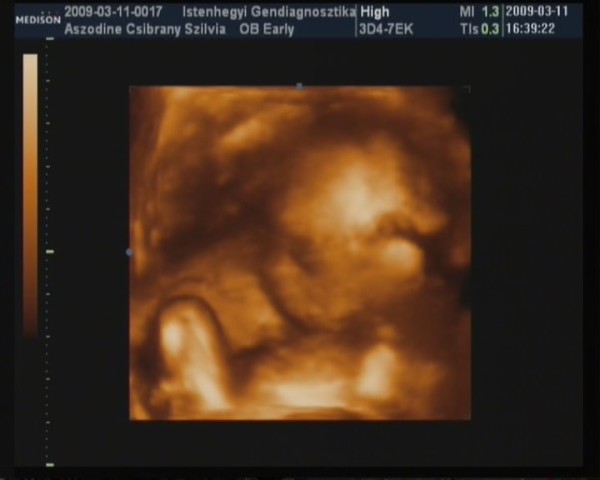

Minden rednben a Picurral és tuti FIÚ!!! :D :D :D

Kb 6 nappal korábbi a koránál igy vszinű átirom a vonalzómat hiszen múlt héten is ugyanennyinek mérték a korát, és a hosszabb ciklusaim miatt simán lehet.

Doki nagyon rendes volt mindent megmutatott majd ha lefényképezem akkor felteszek róla képet.Az arcát nagyon takarta igy nem nagyon tudtak róla szép képet feltenni,de majd májusban amikor megint megyünk 4d-re.